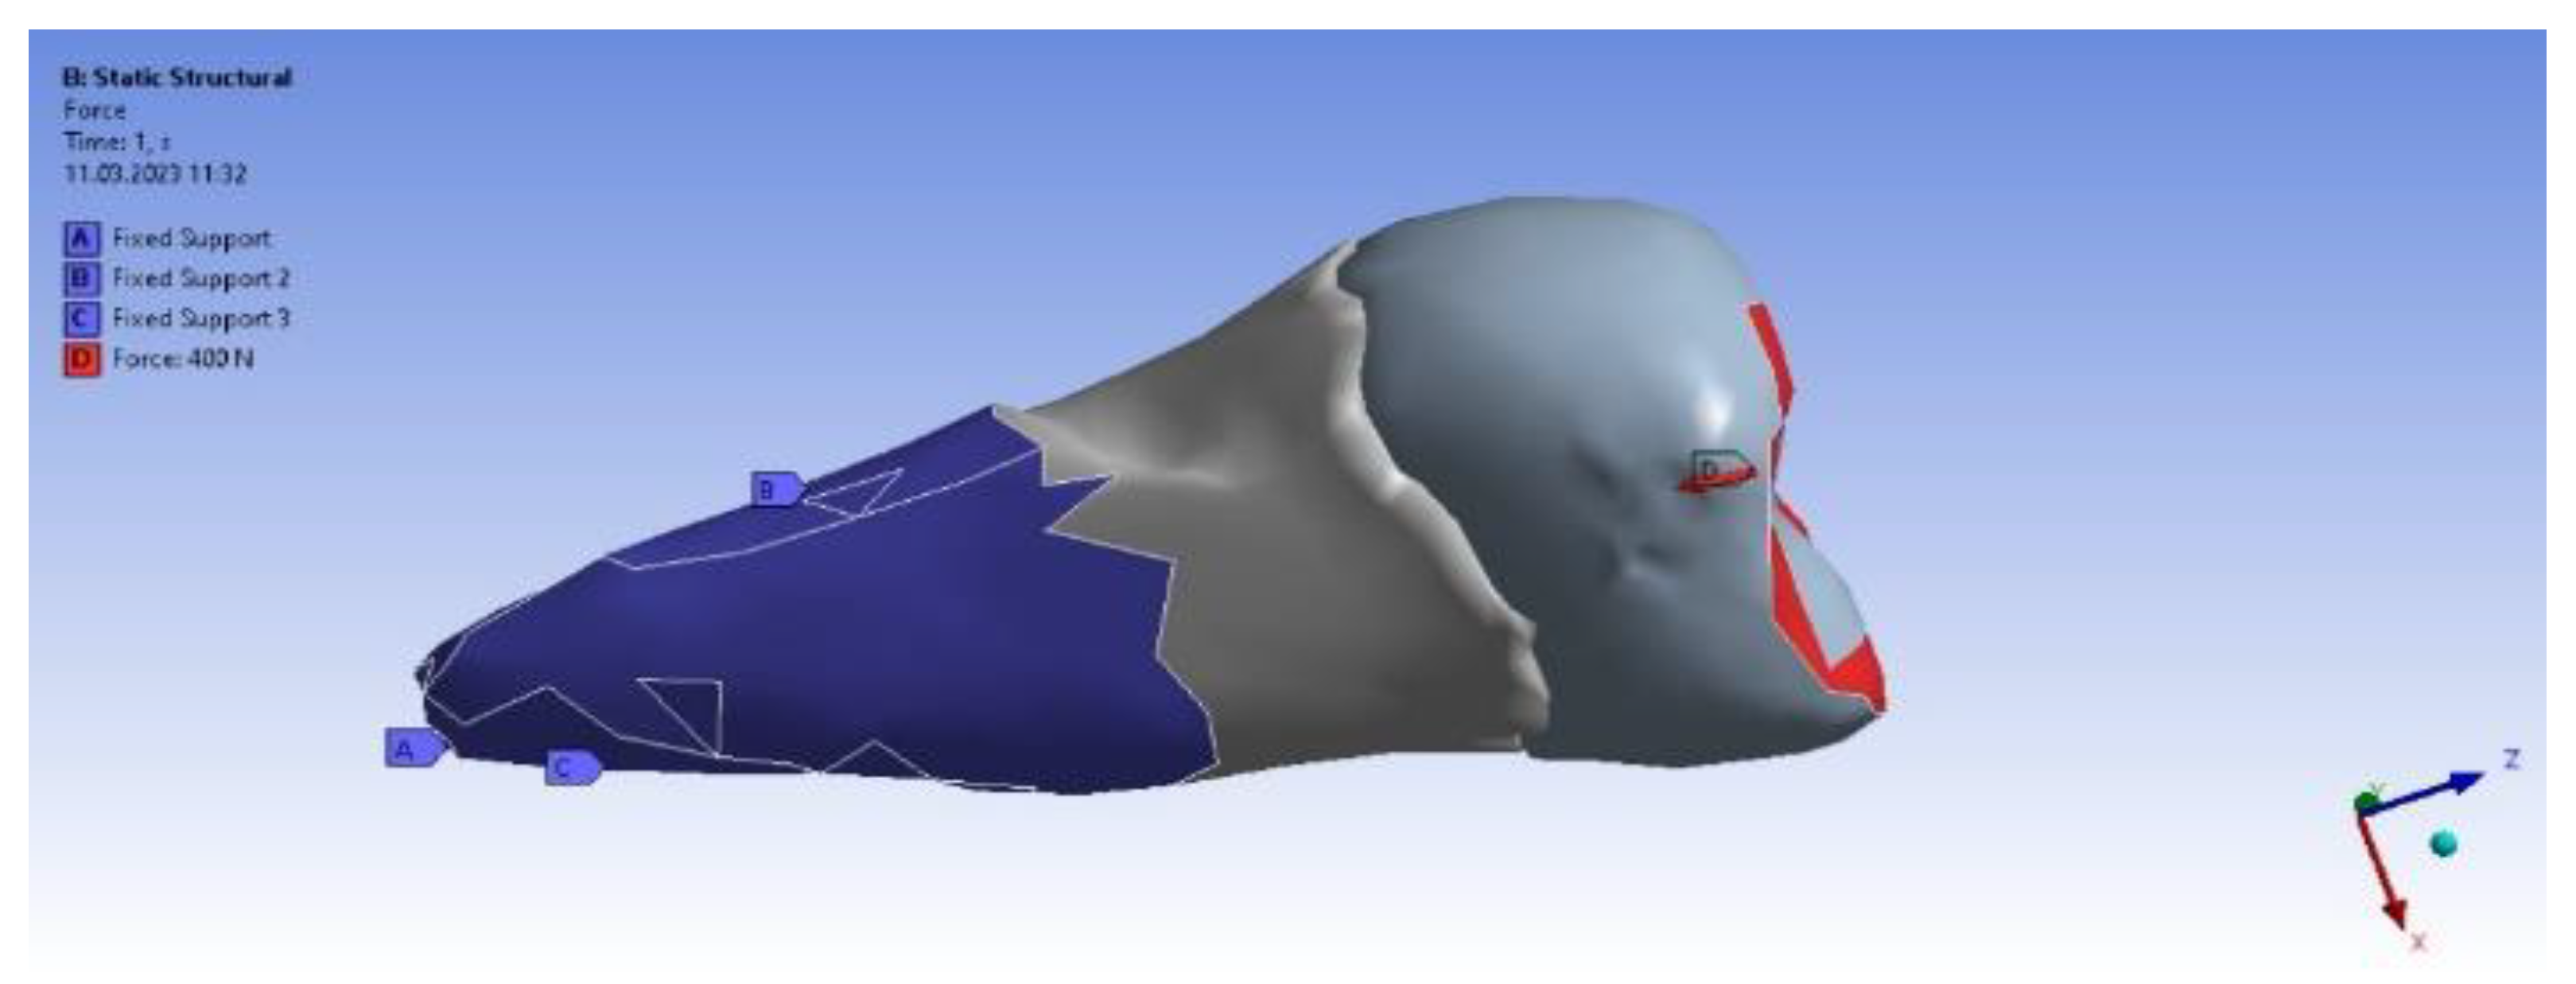

3. Finite Element Analysis (FEA) of Mandibular Right Premolars